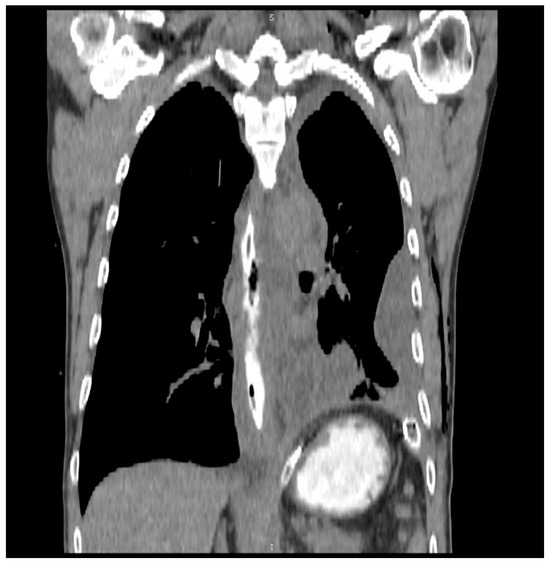

In an era where patient-reported outcomes have become more important, one of the tools that every surgeon should have in their bag is diagnostic laparoscopy. This versatile instrument can serve as a diagnostic confirmation and definitive treatment. Through a couple of trocars placed into the abdomen, a surgeon can diagnose a variety of surgical ailments, such as bowel infarction, the site of obstruction in bowel obstruction, occult hernias, and, last but not least, trauma. In addition, the oncological field is another place where it shines: intraperitoneal tumors, peritoneal carcinomatosis, and superficial liver metastases that were not identified upon imaging. Staging laparoscopy is recommended for pancreatic and gastric cancers, thus providing a potential indication for radical surgery. Laparoscopy is not only diagnostic, but after identifying the nature of the surgical disease one can perform various laparoscopic surgeries with net advantages when compared to the open approach.